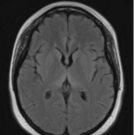

A 26-year-old woman presented to the emergency department (ED) with progressive confusion and recurrent falls. The patient reported having vomiting and diarrhea for 1 week and several falls 1 day before her...

11/30/2024